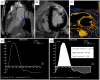

Aortic regurgitation (AR) is a common valvular pathology. Multimodality noninvasive cardiovascular imaging is routinely used to assess the mechanism of AR, degree, and its hemodynamic impact on the cardiovascular system. Collecting this information is crucial in establishing the prognosis and in guiding patient management and follow-up. While echocardiography remains the primary test to assess AR, a comprehensive assessment of this valvulopathy can be obtained by combining the information from different techniques. This state-of-the-art review is intended to provide an update ed overview of the applications, strengths, and limits of transthoracic echocardiography, cardiac magnetic resonance, and cardiac computed tomography in patients with AR.